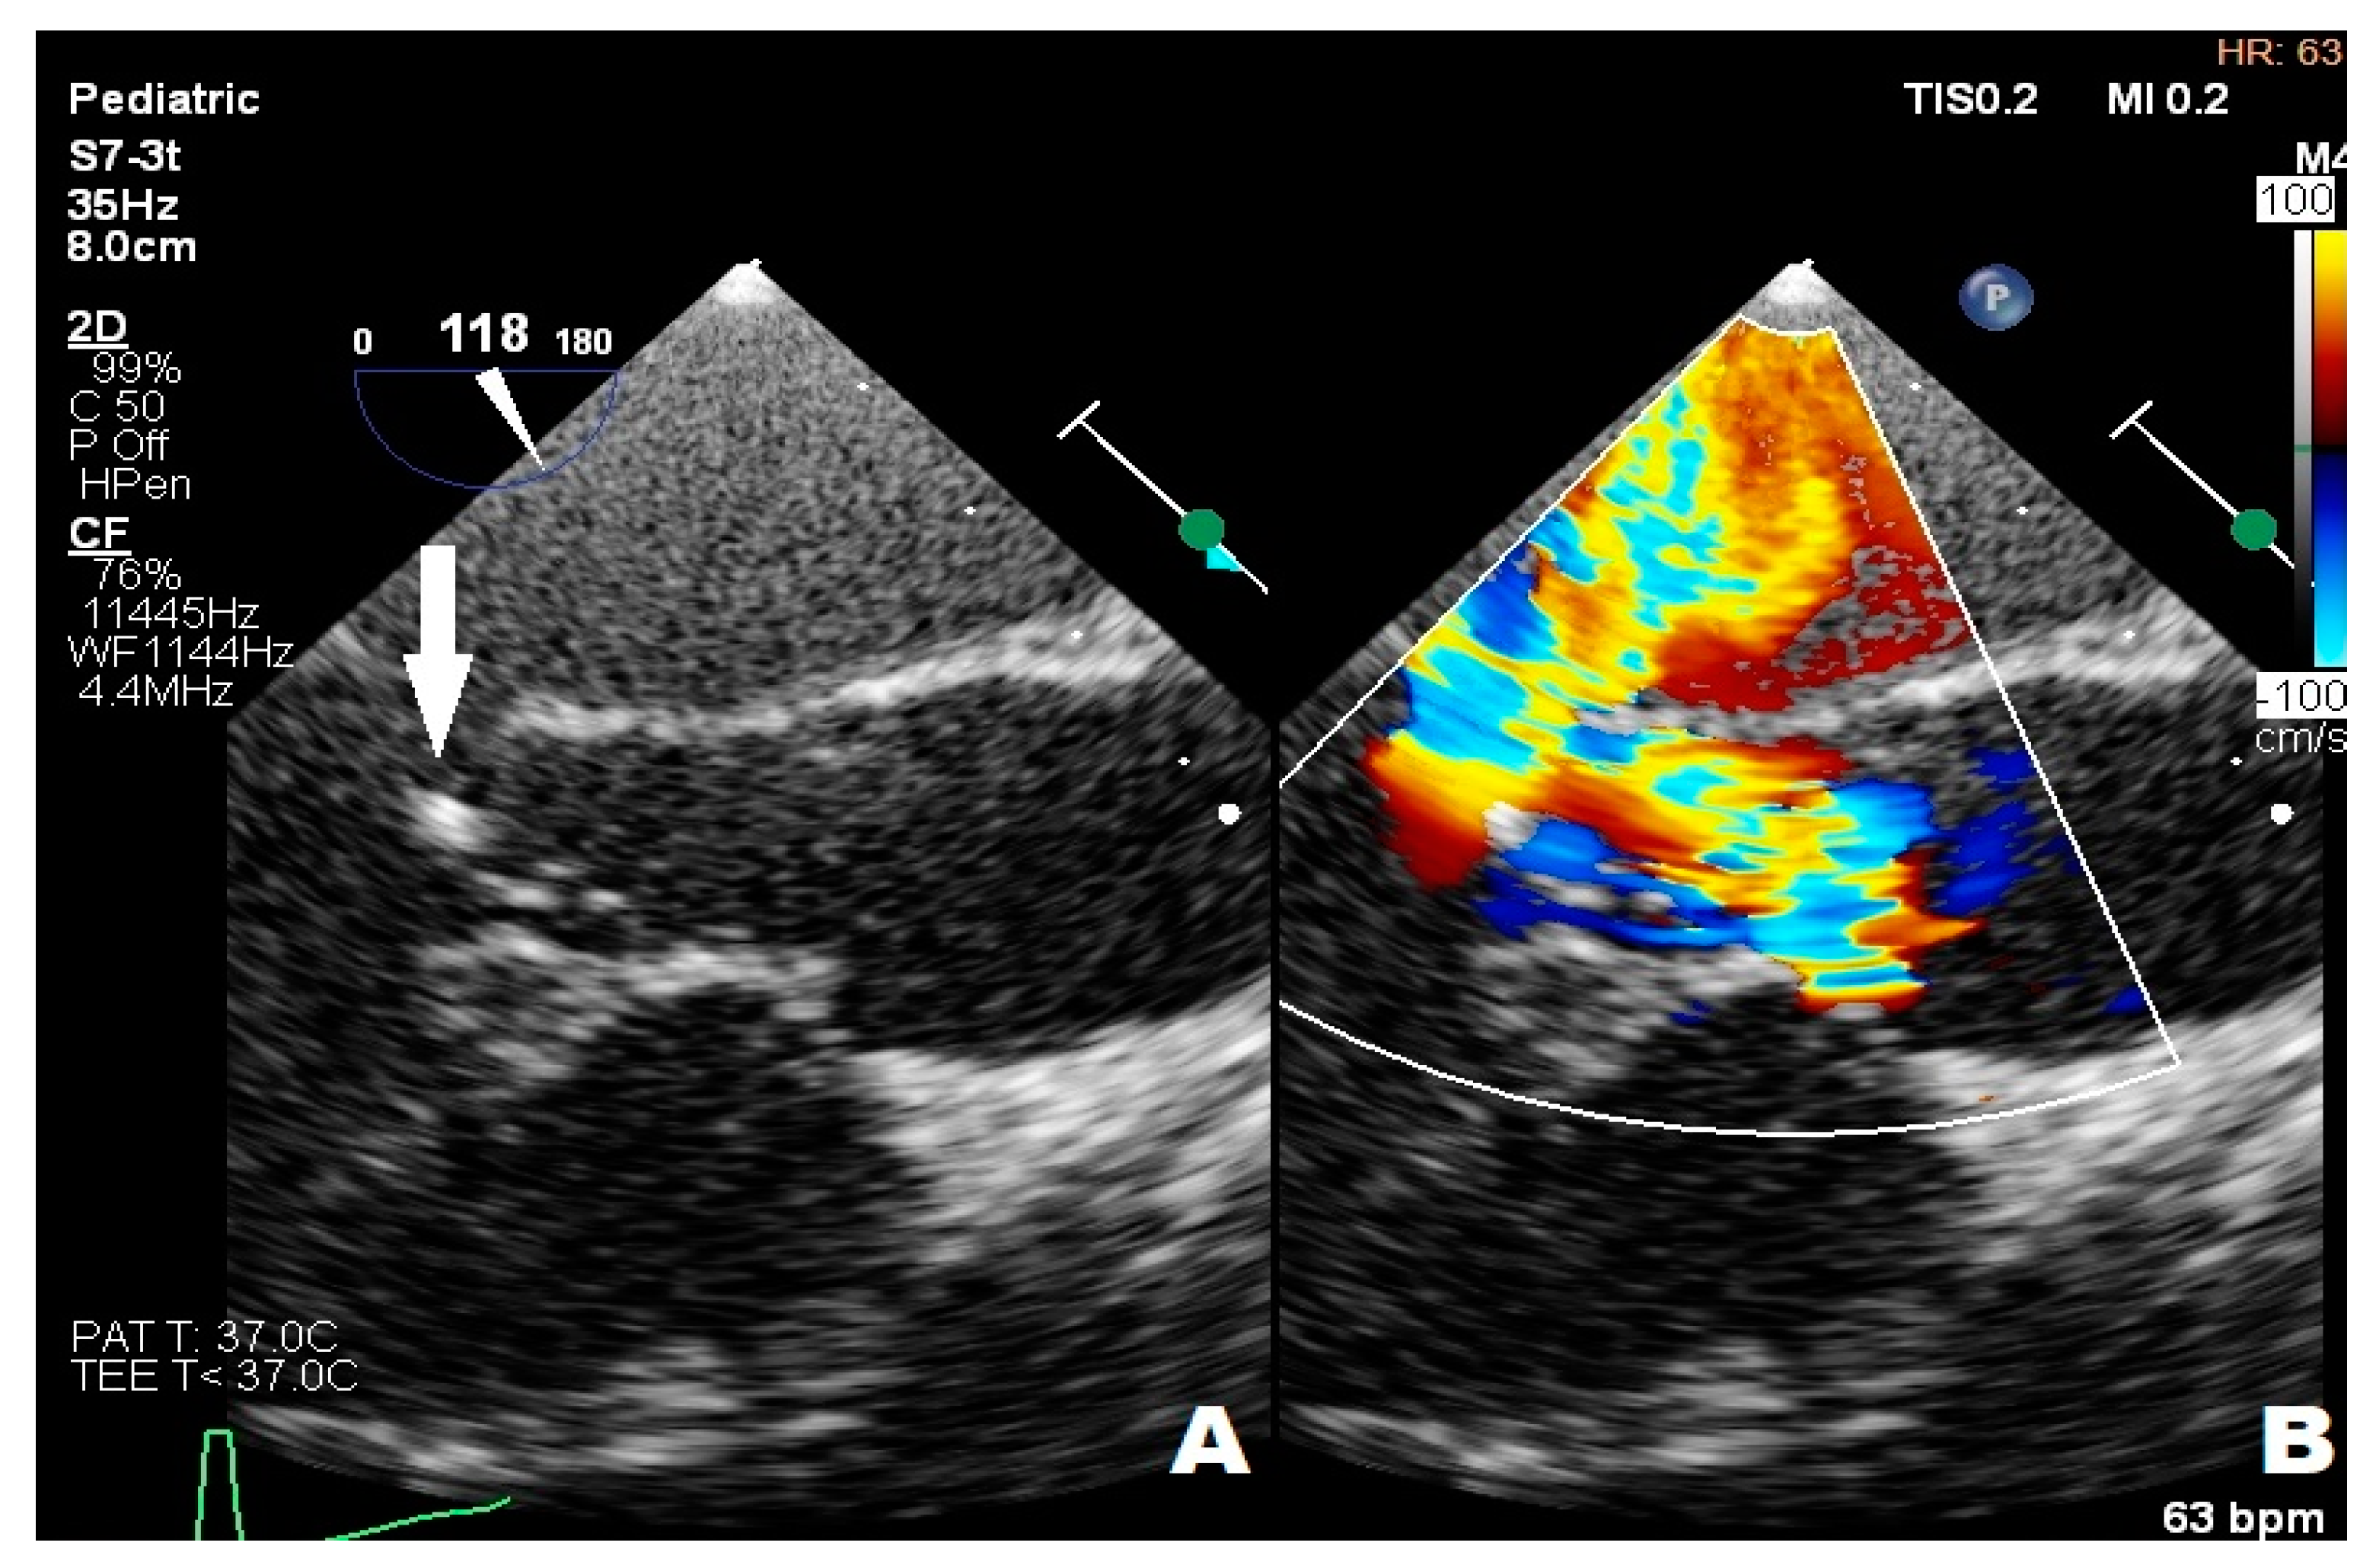

An 11-year-old girl with trisomy 21 underwent complete surgical repair for an atrioventricular septal defect (AVSD) during infancy. She presented with thrombocytopenia (65.0 K/μL), petechia, enlarged chest, and abdomen lymph nodes. The diagnostic process was carried out in the hematology department to confirm the Autoimmune Lymphoproliferative Syndrome (ALPS). The vegetations in mitral and aortic valves were found during routine TTE. Any microbiological pathogen was isolated from blood culture samples. The girl did not present any infectious symptoms. A systolic heart murmur of 3/6 in the LS over the cardiac apex and a diastolic heart murmur of 2/4 over the aortic valve were the only abnormalities upon her physical examination. Furosemide (10 mg twice/day), spironolactone (25 mg/day), captopril (12.5 mg/day), teicoplanin (200 mg/day), ceftriaxone (1.5 g/day), and fluconazole (100 mg/day) were administered as the treatment. In the fourth week of her treatment, the patient was transferred to an upper reference department, where further investigation was undertaken. Thickened mitral leaflets, III degree mitral regurgitation, one hyperechogenic 4 mm × 7 mm lesion in mitral chordae, thickened limited-move right coronary aortic valve leaflet (RCL), and severe eccentric aortic regurgitation were found in repeated TTEs (Figure 2A,B), and the transthoracic echocardiography image was confirmed in TOE (Figure 3A,B). In summary, the patient met one major and one minor criterion in Duke’s guidelines for diagnostics, suggesting the possibility of IE. The repeated blood culture samples were negative and the thrombocytopenia (78 K/μL), leukopenia (3.89 K/μL) with neutropenia (0.93 K/μL), mild anemia (RBC 3.8 M/μL), and elevated CRP level (8.4 mg/L) were observed in laboratory tests. The antibiotic therapy was changed in the fourth week of treatment—ceftriaxone was replaced by gentamicin (60 mg/day) due to a persistent elevated CRP level, leukopenia, neutropenia, and anemia, which could be attributed to common side effects of ceftriaxone. During the whole period of hospitalization, the girl felt well, but temporarily elevated creatinine levels, thrombocytopenia, and leukopenia were observed. The girl left the Pediatric Cardiology Department in good condition and with reduced inflammatory indicators in blood tests after the full 6-week treatment, and was qualified for cardiac surgery after full dental treatment and ALPS exclusion.

Figure 2.

Transthoracic echocardiography; (A) arrow point at the mitral regurgitation wave; (B) arrow point at hyperechogenic 4 mm × 7 mm lesion in mitral chordae.

Figure 3.

Transesophageal echocardiography; (A) the arrow point at vegetation; (B) mitral regurgitation wave, aortic regurgitation wave.